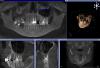

vuser Опубликовано 26 сентября, 2013 Автор Поделиться Опубликовано 26 сентября, 2013 (изменено) ...странные люди...с оптикой но без коффера... с коффером, но без оптики...Лучше поищите доктора. Успехов. А вы терапевт? То есть ничего страшного не видите? Вот ещё снимок Изменено 26 сентября, 2013 пользователем vuser Ссылка на комментарий

x3m Опубликовано 26 сентября, 2013 Поделиться Опубликовано 26 сентября, 2013 а чего сразу на вынос?почему не попытаться вылечить?тем более, что ничего ужасного не видно.Скорее всего, есть дополнительный (4-й) канал в корне, вокруг которого воспаление. Ссылка на комментарий

vuser Опубликовано 26 сентября, 2013 Автор Поделиться Опубликовано 26 сентября, 2013 а чего сразу на вынос?почему не попытаться вылечить?тем более, что ничего ужасного не видно.Скорее всего, есть дополнительный (4-й) канал в корне, вокруг которого воспаление.Про 4 канал так и есть, КоТэ это подтверждает. Просто мой доктор сказала, что мол- лечение сравнимо с имплантацией (хотя мне кажется куда дешевле)- сложно предсказать результат- есть риск трещины при паковке- ухода материала в пазуху при распаковке- гайморита после лечения. Возможно стоит попробовать другого доктора. Ссылка на комментарий